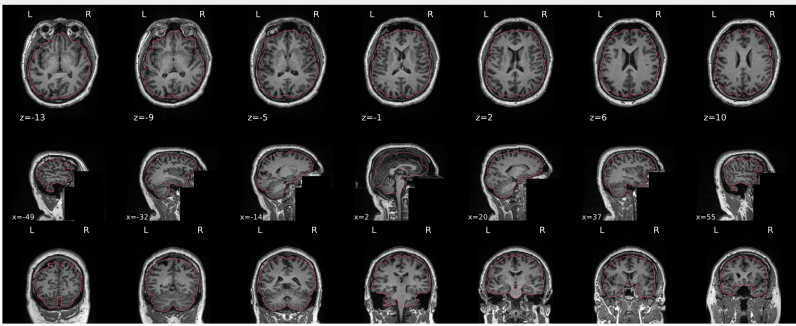

T1w skull stripping

Skull stripping is the process separating the brain (cortex and cerebellum) from the skull. The red line follows the outline of the brain and it separates it from the skull.

Example of a good subject

- There are no skull stripping errors, such as portions of the brain missing, or too much of the skull retained

- The red line follows the outline of the brain

Example of a bad subject

- There are skull stripping errors, such as portions of the brain missing, or too much of the skull retained

- NOTE: check all the images (slices) in the report. If only one image (slice) looks problematic, it is possible that the subject is okay and it is just a visual issue in that particular screenshot

Summary

| Good | Bad |

|---|---|

| The brain is fully inside the red line | Structures like the cranium or the eyes are inside the red line |

| No important brain structures are outside of the red line red line follows the natural outline of the brain | Important brain structures are missing inside of the red line |

-> if only one slice is problematic, it could be an issue related to the visual depiction of the data instead of an issue related to the test subject